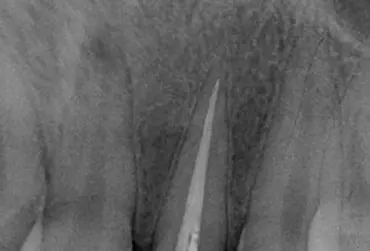

Ekstruzja ortodontyczna alternatywa dla postępowania chirurgicznego

Ekstruzja ortodontyczna zaczyna być coraz bardziej powszechnie stosowaną metodą w celu uniknięcia postępowania chirurgicznego. Nazywa się ją często wymuszonym wyrzynaniem.